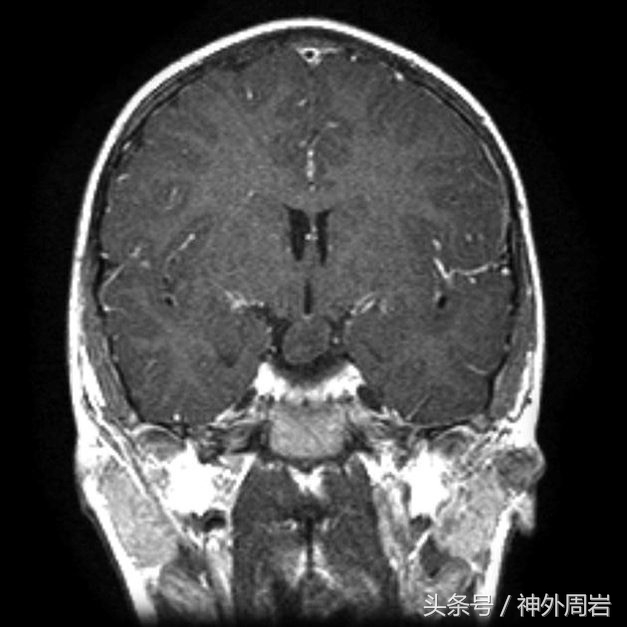

主要发生在5岁以下,除了发笑以外,无情绪变化和意识障碍,几乎不伴有其他癫痫症状,多有下丘脑错构瘤,如进一步压迫下丘脑,患者还可出现性早熟症状。

这类患者对药物治疗反应不好,预后差,早期手术切断错构瘤与周围组织的病理联系可减少或终止发作。